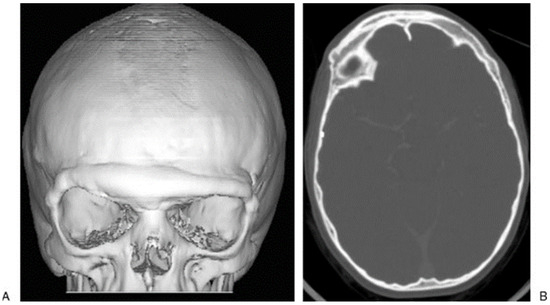

If the TMJ is functioning well but there has been disturbance to the growth potential of the mandible, facial asymmetry and/or malocclusion may occur. Treatment may be solely orthodontic or may involve orthognathic surgery (Figure 8). Long-term records of 88 children who sustained mandibular fractures and presented to the Hospital for Sick Children were retrospectively reviewed to assess the need for later orthodontic treatment or orthognathic surgery [12]. Results indicated that a pediatric mandibular fracture does not lead to a higher incidence of orthodontic treatment. Children younger than 4 years or older than 12 years rarely require orthognathic surgery to correct facial growth disturbances following mandibular fractures. In contrast, 22% of children aged 4 to 7 years and 17% of children aged 8 to 11 years required orthognathic surgery to correct facial growth disturbances following mandibular fractures. Condylar fractures were the most common site of mandibular fracture and led to facial asymmetry most frequently.

Figure 8. (A) This 3-year-old patient sustained a left parasymphyseal fracture and right condylar head fracture following a fall down stairs. The parasymphyseal fracture was plated and she was mobilized on a soft diet. (B,C) Seven years later, she was noted to have mandibular asymmetry with the chin point deviating to the right side suggestive of right-sided undergrowth. Cephalometric analysis showed decreased height of the posterior ramus on the right side. She underwent bilateral sagittal split osteotomies to correct this asymmetry.